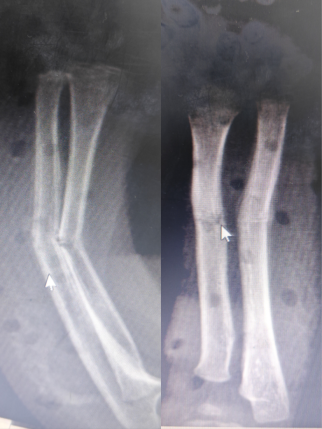

杜龙龙医生接诊后,仔细查阅患儿的病历与影像资料,又轻柔地为孩子进行体格检查。检查发现,患儿左前臂压痛显著,畸形突出,结合X线片显示的尺桡骨骨折断端移位、成角畸形等情况,诊断结果明确。考虑到陈旧性骨折因软组织粘连、骨痂已开始形成,手法复位难度远超新鲜骨折,加之患儿年龄较小,骨骼娇嫩脆弱,操作中稍有不慎便可能造成二次损伤。杜龙龙医生当即向董博主任和周健主任汇报病情,两位主任迅速赶到诊室,三人共同展开病情研判。为最大程度减轻孩子的痛苦,三位医生反复斟酌,制定了周密的复位方案,并向家属详细说明复位过程中的风险与预期效果,在取得家属知情同意后实施操作。

复位过程中,三位医生分工协作、配合默契。他们先轻柔按摩患儿前臂软组织,缓解肌肉紧张与粘连;随后通过持续牵引拉开骨折断端,为复位创造空间;最后精准运用折顶、旋转等专业手法,一步步纠正骨骼畸形。整个过程动作连贯、力度精准,仅数分钟便完成复位。复查X线片显示,骨折断端对位对线良好,患肢外观恢复正常。医生随即为患儿进行石膏固定,并详细指导家属观察血液循环、定期复查及早期功能锻炼等注意事项。董博主任特别叮嘱:“幼儿骨折愈合速度快,但陈旧性骨折的康复需要更密切的随访,我们会定期跟踪孩子的康复情况,及时调整护理方案,确保骨骼正常生长发育。”